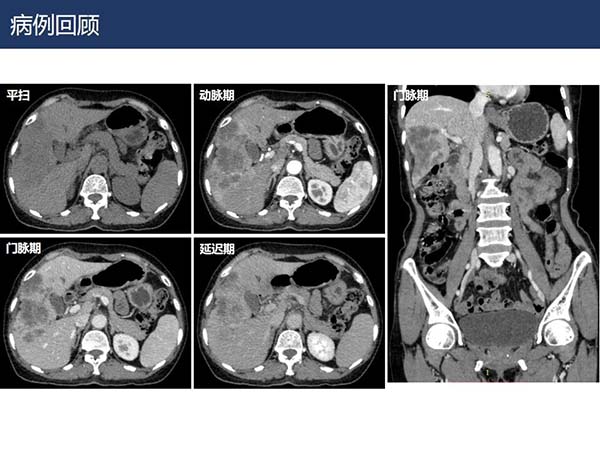

【杨柳病例】肝内胆管细胞癌的影像表现